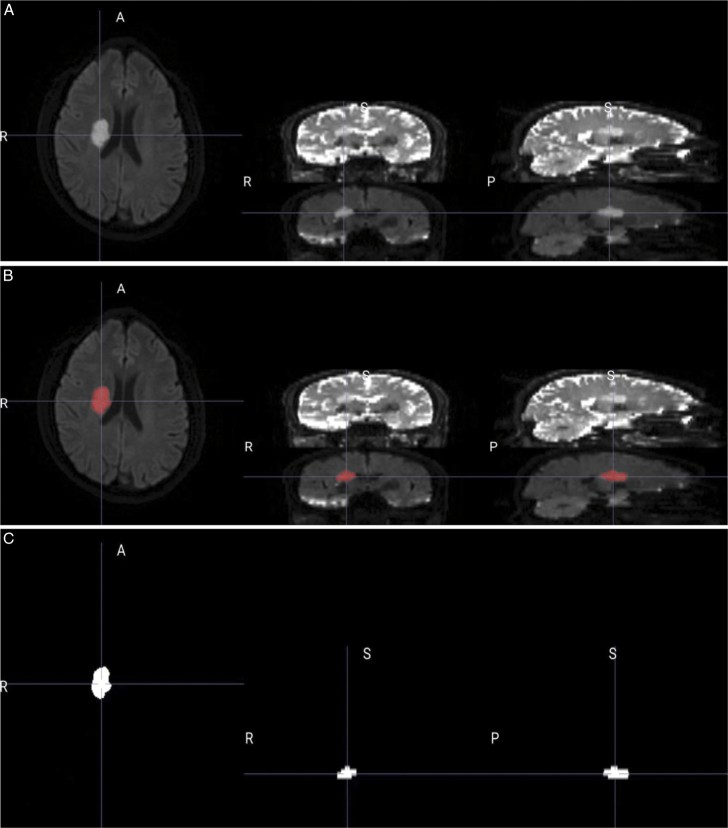

Patients and methods: We enrolled a total of 171 patients with AIS in this study, including 134 patients with a good prognosis and 37 patients with a poor prognosis, and collected the patients' clinical and DWI image data. Radiomics features from manually sketched ischemic lesions were extracted using the Pyradiomics package of Python, and the best radiomics features were selected by a t test and the least absolute shrinkage and selection operator. The radiomics model and clinical model were constructed using support vector machine and logistic regression, respectively, and the predictive performance of each model was evaluated.

Abstract Image